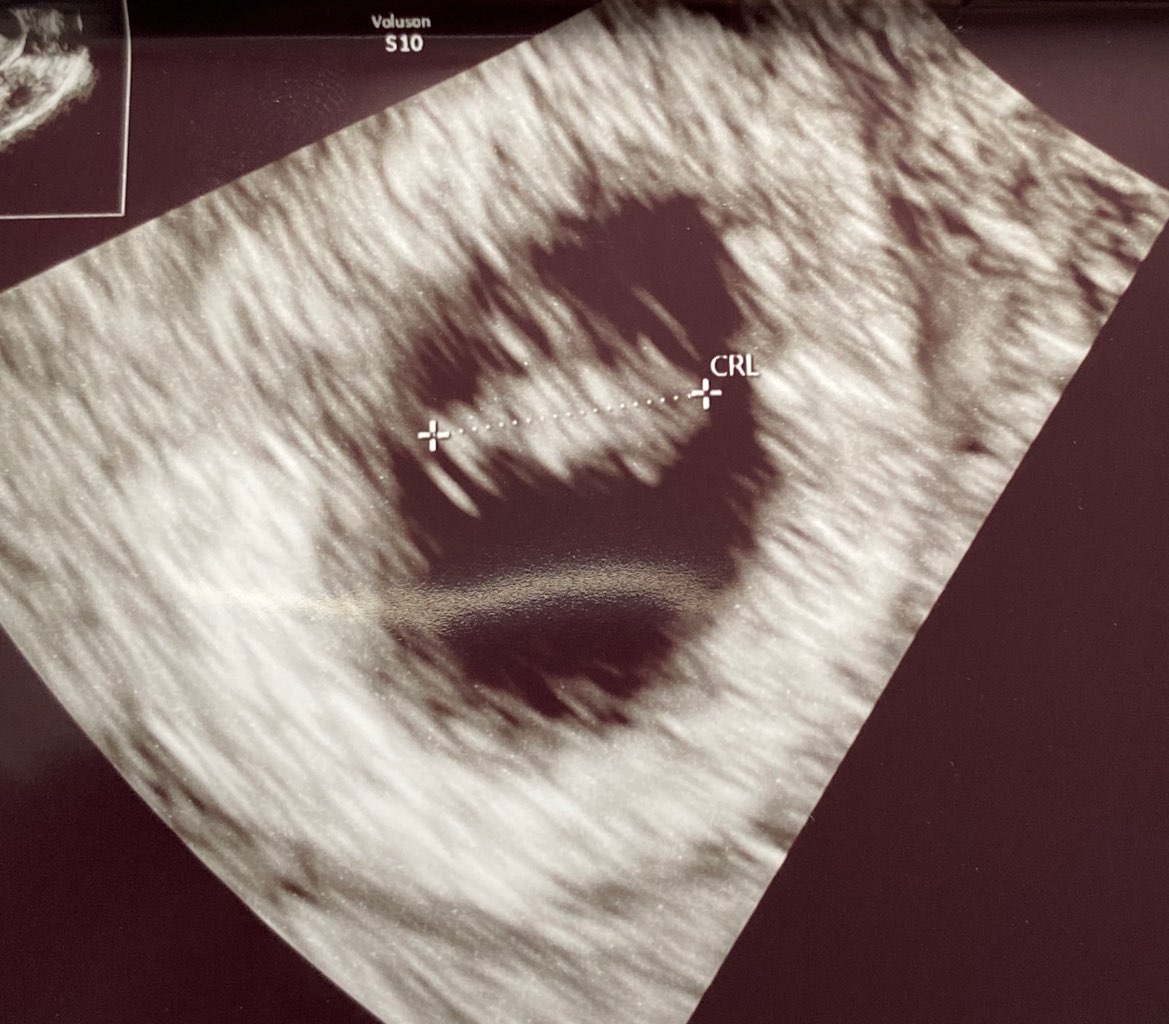

Moje serce pięknie bije! Mam 7 tyg i 1 dzień ❤️❤️❤️

• IMG_4250.jpeg

IMG_4250.jpeg

161,7 KB · Wyświetleń: 111